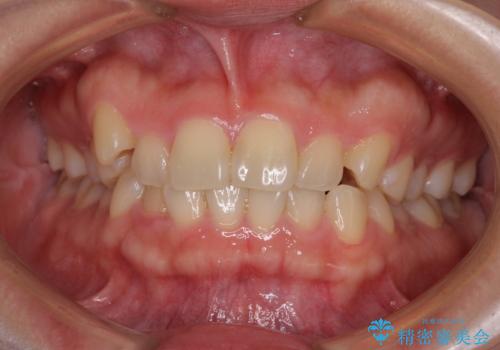

八重歯を治す 非抜歯のワイヤー矯正治療

- 左右の八重歯を気にして来院された患者様です。

ワイヤー装置でもマウスピースでも対応可能な歯列でしたが、マウスピース矯正は自己管理が煩わしいとのことでワイヤー矯正を選択されました。

八重歯である犬歯は歯根が長いため、上顎前歯が出っ歯になるリスクがあるため、必要に応じてアンカースクリューを用いて奥歯を後方に移動させる可能性をお伝えしました。

舌の突出癖により上下前歯が開咬となりましたが、舌のトレーニングと顎間ゴムの使用により、元々の被蓋関係に改善することができました。

アンカースクリューを用いて、出っ歯仕上がりを回避し、正中位置も改善することができました。